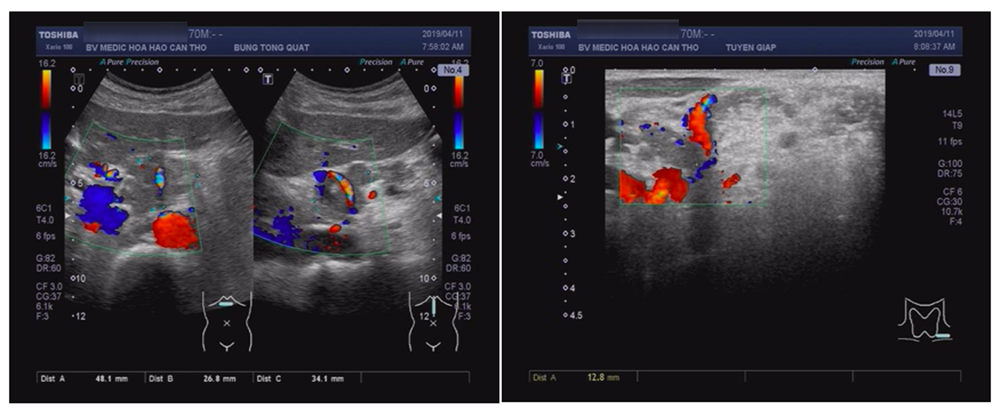

Siêu âm

Dày vách thực quản đoạn tâm vị 15mm, chùm hạch lớn 5cm vùng cạnh đầu và thân tụy.

Hạch dạng di căn 12mm vùng thượng đòn trái.